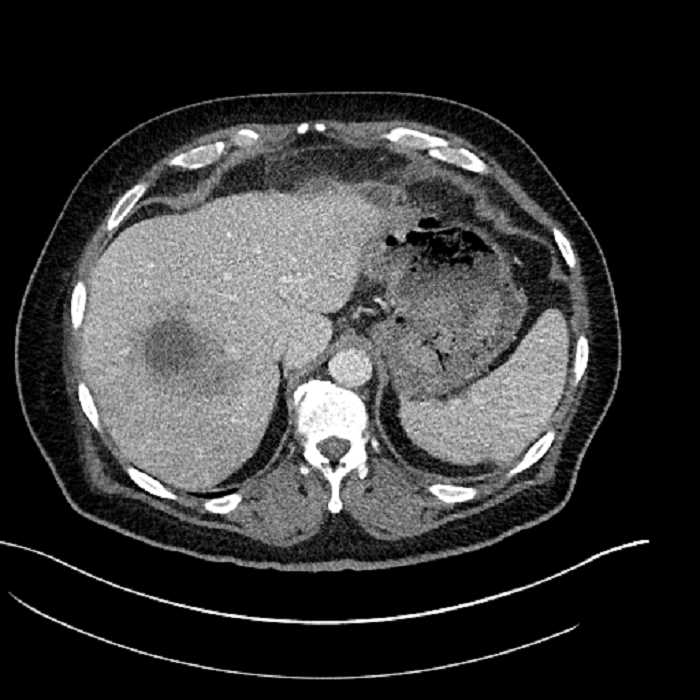

• Large fluid density structure in hepatic segments 7 and 8 measuring 10 x 7 x 7 cm with internal septation and circumferential ill-defined low density compatible with edema

• Clearly marginated fluid density structure in segment 7 and several other scattered tiny hypodensities, which likely represent cysts

• Hepatic abscess

Acute sigmoid diverticulitis complicated by a small contained perforation and a large abscess in the right hepatic lobe. Additional small subcapsular abscesses along the anterior margin of the left hepatic lobe.

• The classic CT imaging appearance is a double target sign with internal low density surrounded by an internal enhancing rim (capsule) and a low density external rim (edema)

Hepatic abscess showing the double target sign with low density internally surrounded by a thin inner enhancing rim (red arrow) and ill-defined outer low density rim (yellow arrow). Blue arrow indicates an internal septation. Red arrows: additional smaller subcapsular abscesses. Red arrow: focal contained perforation associated with diverticulitis.